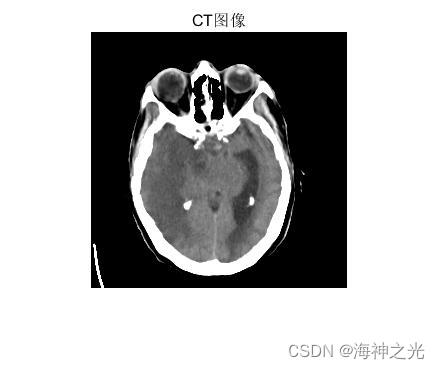

(2)多模态医学图像融合:将不同模态的医学图像进行融合,可以提供更全面和准确的医学诊断信息,有助于医生做出更准确的判断和决策。

多模态图像融合(如:红外和可见光图像的融合;医学图像的融合)

彩色医学图像融合是指将多幅彩色医学图像融合成一幅综合图像,以提供更全面、更准确的信息。NSST和PCNN可以结合使用来实现彩色医学图像融合。具体原理如下: